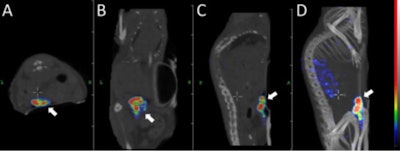

For the study, the Affibody-based pretargeted peptide nucleic acid (PNA) labeled with lutetium-177 (Lu-177) was evaluated in mice bearing xenografts that express human epidermal growth factor receptor 2 (HER2). The experimental radionuclide therapy was then tested on mice in six cycles separated by seven days (JNM, July 2018, Vol. 59:7, pp. 1092-1098).

The researchers observed rapid clearance of Lu-177 PNA from most tissues, with prominent uptake in the kidneys and the tumor. More importantly, tumor uptake was four times greater than renal uptake at one hour postinjection. In addition, 84% of the renal uptake cleared with a 15-minute half-life, compared with a tumor clearance half-life of 63 hours.